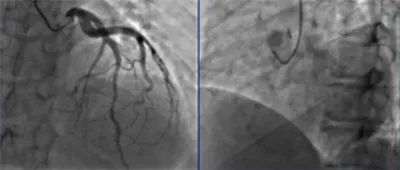

冠脉造影,如下图所示。

主动脉CTA造影,如下图所示。